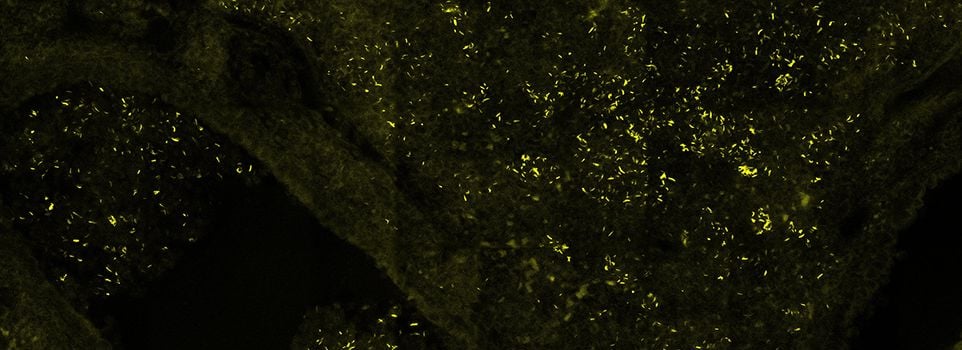

Systems Genetics of Tuberculosis

Tuberculosis remains a serious threat to global health. The development of transformational new interventions for this disease relies on understanding the fundamental biology that determines the pathogenesis of the disease. We are a diverse group of bacteriologists, immunologists, and geneticists that are focused on understanding the critical interactions between Mycobacterium tuberculosis and its human host that determine disease progression and treatment response.